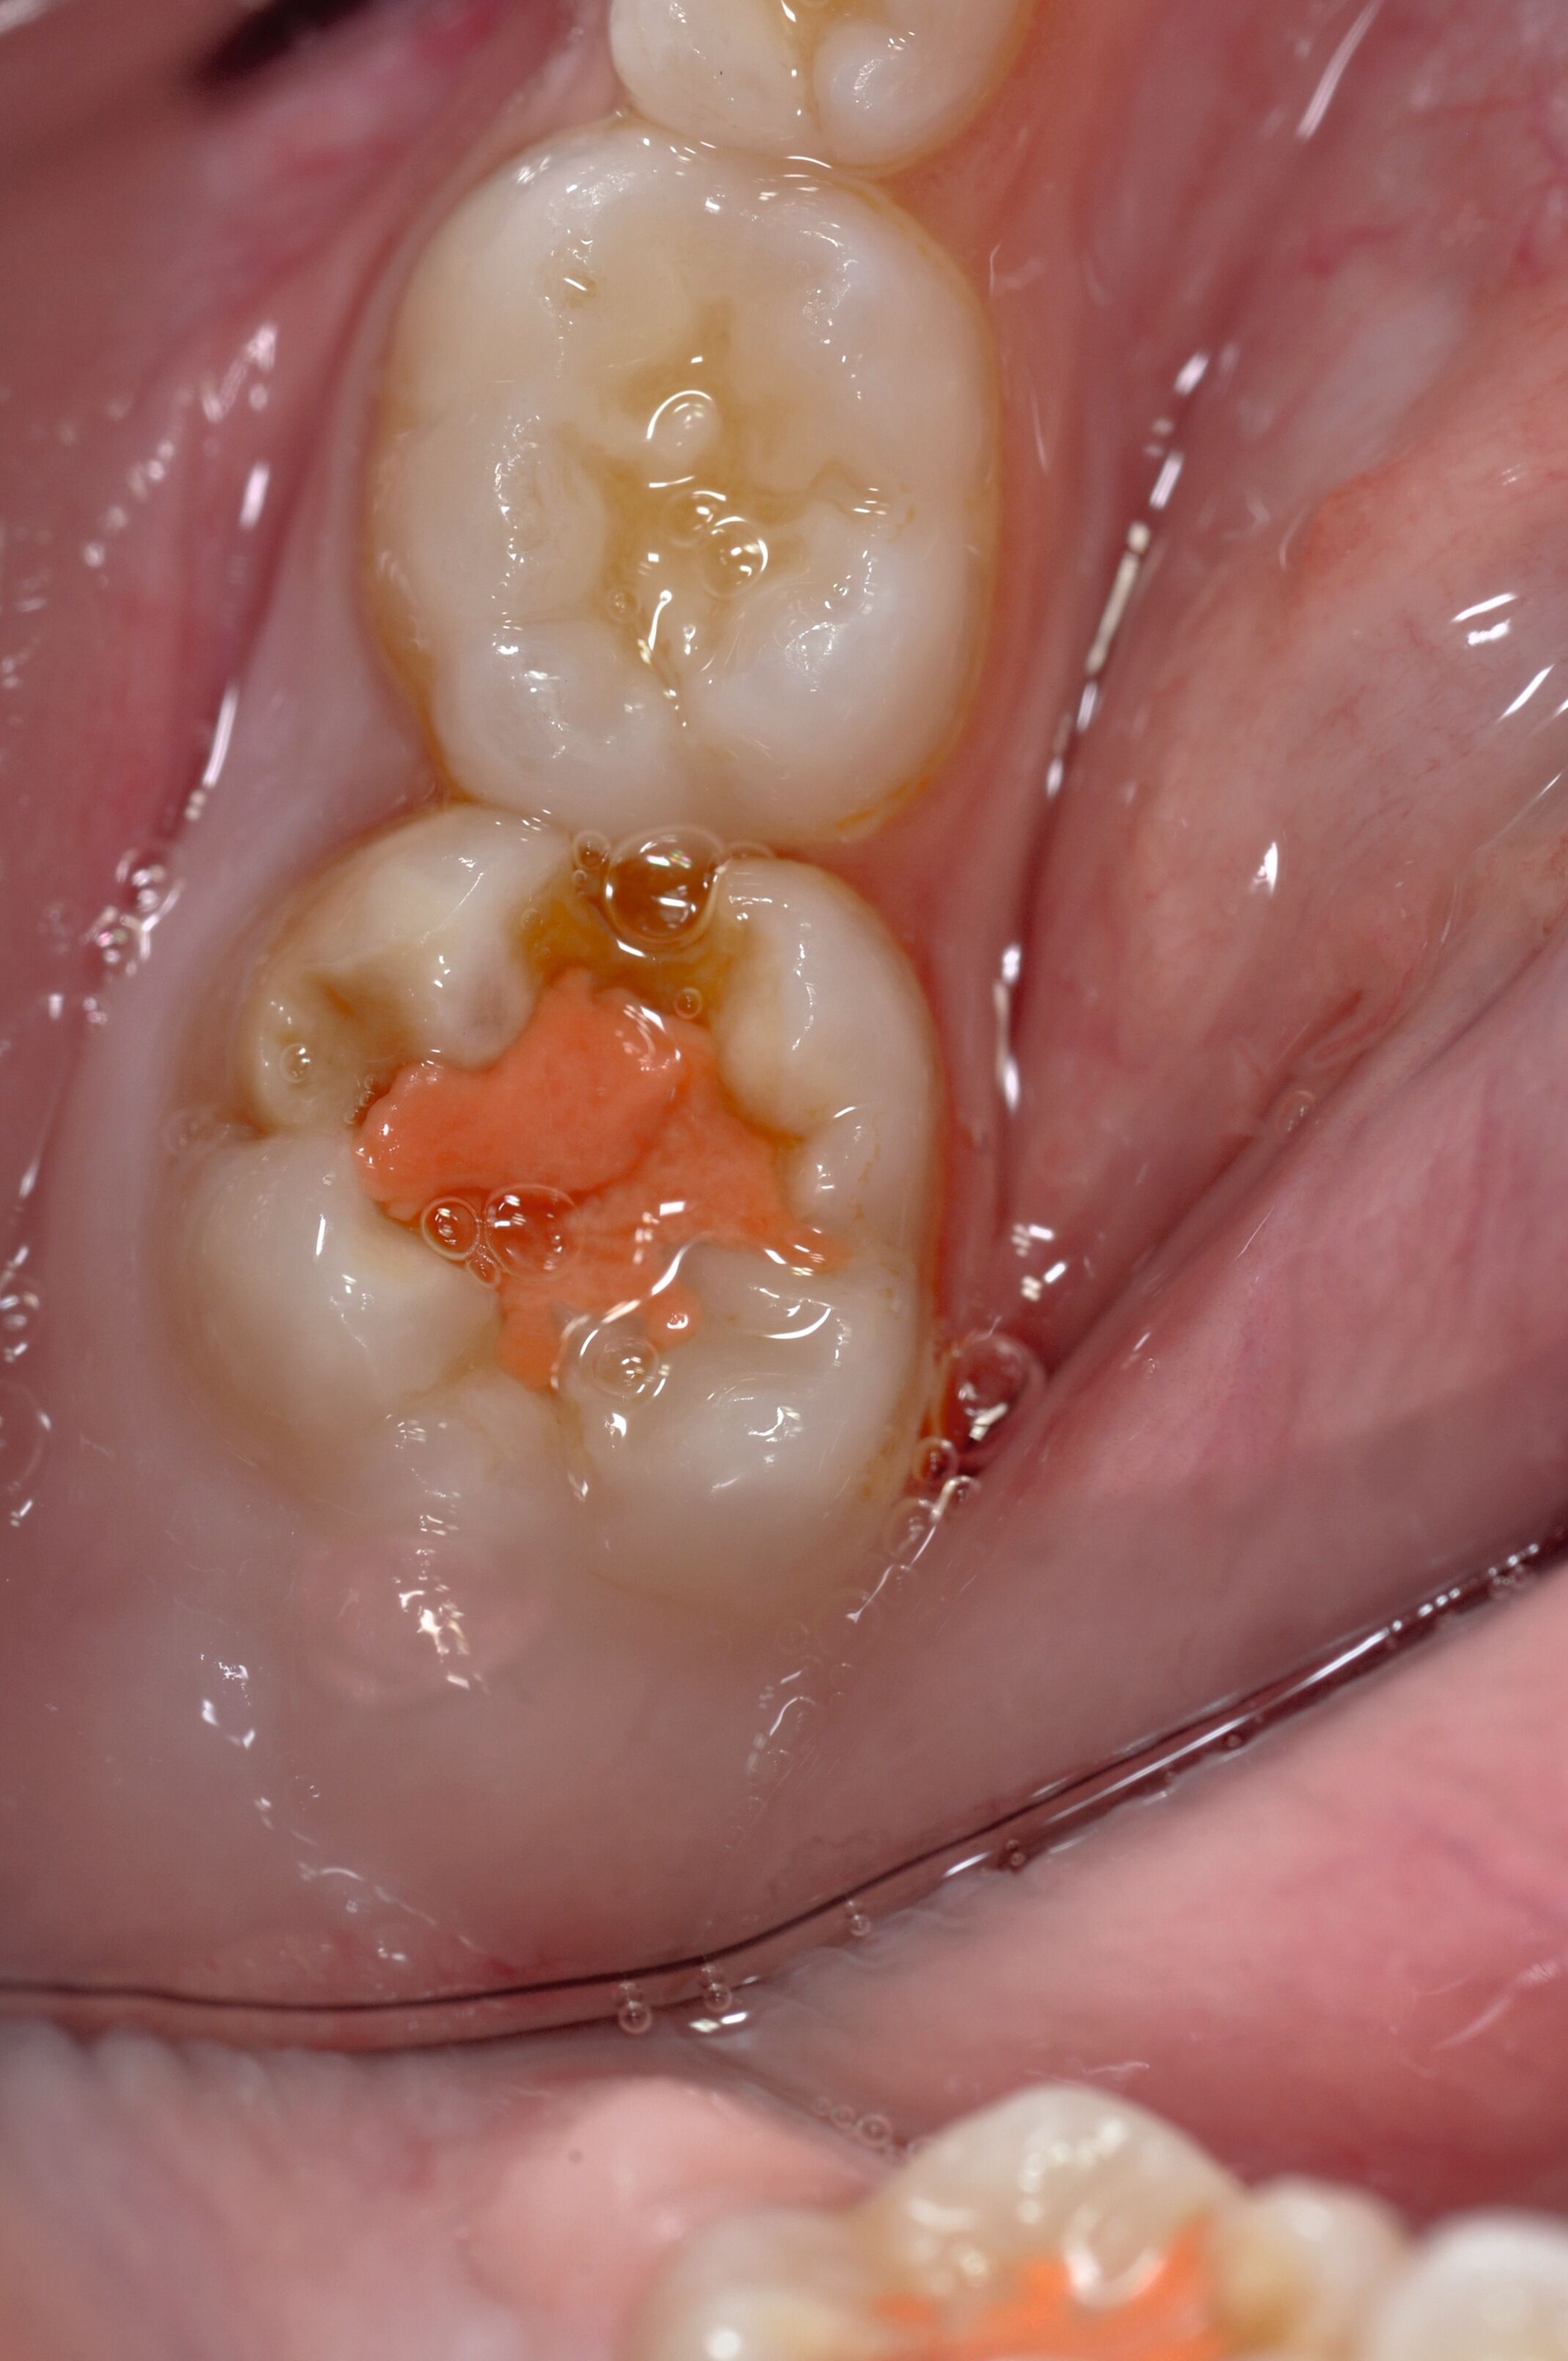

Mit der Einführung von Silberdiamminfluorid (SDF) als 38-prozentige Lösung wurde ein Verfahren vorgestellt, welches die Kariesprogression stoppt und zusätzlich zur Desensibilisierung überempfindlicher Zähne beiträgt [Seifo et al., 2020]. Seifo et al. beschrieben in einer Übersichtsarbeit, dass silberionenhaltige Präzipitate die freiliegenden Dentintubuli verschließen und das im SDF enthaltene Fluorid zur Bildung einer Kalziumfluoriddeckschicht auf der Dentinoberfläche beiträgt [Seifo et al., 2019].

Dieser gewünschte Effekt hat dazu geführt, dass SDF insbesondere bei der temporären Versorgung von hypersensiblen MIH-Molaren mit freiliegenden Dentinoberflächen eine zunehmend bedeutsame Rolle spielt [Erbas et al., 2024; Linner et al., 2020; Saad et al., 2024; Seifo et al., 2019].

Allerdings muss dazu die Dentinoberfläche freiliegen, so dass der oben genannte Effekt auch wirken kann. Dabei wird die behandelte Oberfläche nach der Applikation von SDF mit einem GIZ abgedeckt. Diese Technik ist eine Modifikation der klassischen Applikation von ausschließlich SDF und wird als SMART-Technik (silver modified atraumatic restorative technique) bezeichnet [Lall M, 2024].

Mittlerweile gelingt es, mithilfe der SMART-Technik die Überempfindlichkeit der betroffenen Zähne wirksam zu reduzieren [Erbas et al., 2024; Lall M, 2024]. Abbildung 5 zeigt exemplarisch den Behandlungsverlauf bei einem sechsjährigen ängstlichen Patienten mit kälte- und berührungsempfindlichen Sechsjahrmolaren.